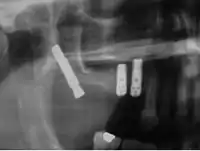

Cigomáticos

Son implantes autorroscantes de longitudes entre 30 a 52,5 mm y una cabeza angulada de 45° que se introducen en el hueso cigomático. Su porcentaje de éxito varía entre 80 y 95 % .Son una alternativa a los injertos de hueso en maxilar atróficos.

Los implantes cigomáticos deben ser colocados por equipos expertos de cirujanos maxilofaciales. Dichos implantes de se colocan bajo anestesia general siempre después de un completo examen quirúrgico y un estudio oral integral completo, que debe incluir modelos dentales del paciente, rayos X y fotos dentales.